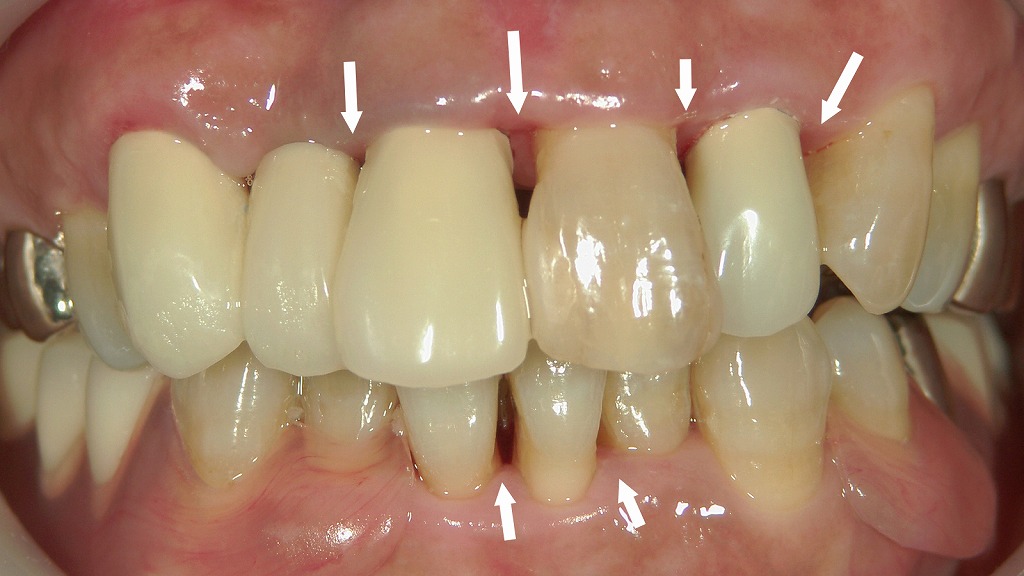

◆ 術後:歯周治療と差し歯の再製作で自然な前歯に回復

こちらは歯石除去と歯周治療を行い、前歯の補綴物(差し歯)を新しく作り直した後の状態です。歯ぐきの炎症が落ち着き、赤みや腫れが改善しています。清掃しやすい形態に整えたことで、歯と歯ぐきの境目がスムーズに仕上がり、プラークがたまりにくくなっています。

前歯の形や色も自然になり、歯列全体のバランスが整ったことで、見た目と機能の両方が大きく改善しているのがわかります。